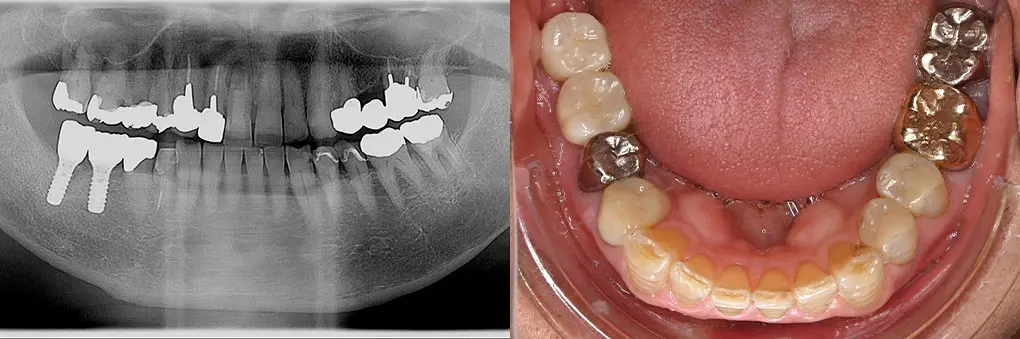

【症例1】All on Fourでインプラント埋入と固定式ブリッジを1日で装着(70代女性)

| 主訴・背景 | 下の前歯がぐらぐらして入れ歯で咬めない |

|---|---|

| 診断・治療前の状態 | 長年義歯を使用していたので下顎臼歯部歯槽骨が吸収 |

| 治療方針・計画 | 抜歯、即時インプラント埋入、即時荷重のAll on Fourで当日固定式ブリッジを装着 |

| 手術・処置内容 | ⚫︎ インプラント埋入部位32,35,42,45 インプラント4本 ⚫︎ 下顎前歯部歯槽骨骨整形、骨造成術 ⚫︎ Nobel Biocare社 ⚫︎ 歯肉付き硬質レジン歯ブリッジ |

| 治療期間・回数 | 仮歯装着まで1日、最終補綴物まで3カ月/治療回数5回 |

| 費用・料金(自費診療の場合) | 2,150,000円 |

| リスク・注意点・術後ケア | 硬質レジン歯の破折、インプラント周囲炎、定期検診 |

| 治療後の状態・経過写真 | 入れ歯による咬合時の痛みがなく、入れ歯と違ってよく咬める 8年経過良好で定期検診に6カ月毎来院 |

| まとめ・院からのコメント | 予算の関係上、人工歯に硬質レジン歯を選択したため咬耗した人工歯交換を次回定期検診時行う予定です。 |